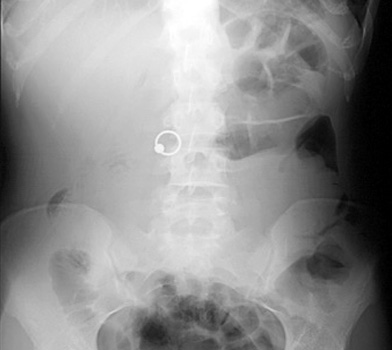

1. This patient presents with acute abdominal pain. What is the most likely diagnosis?

Intussusception Appendicitis Small Bowel Obstruction Malrotation |